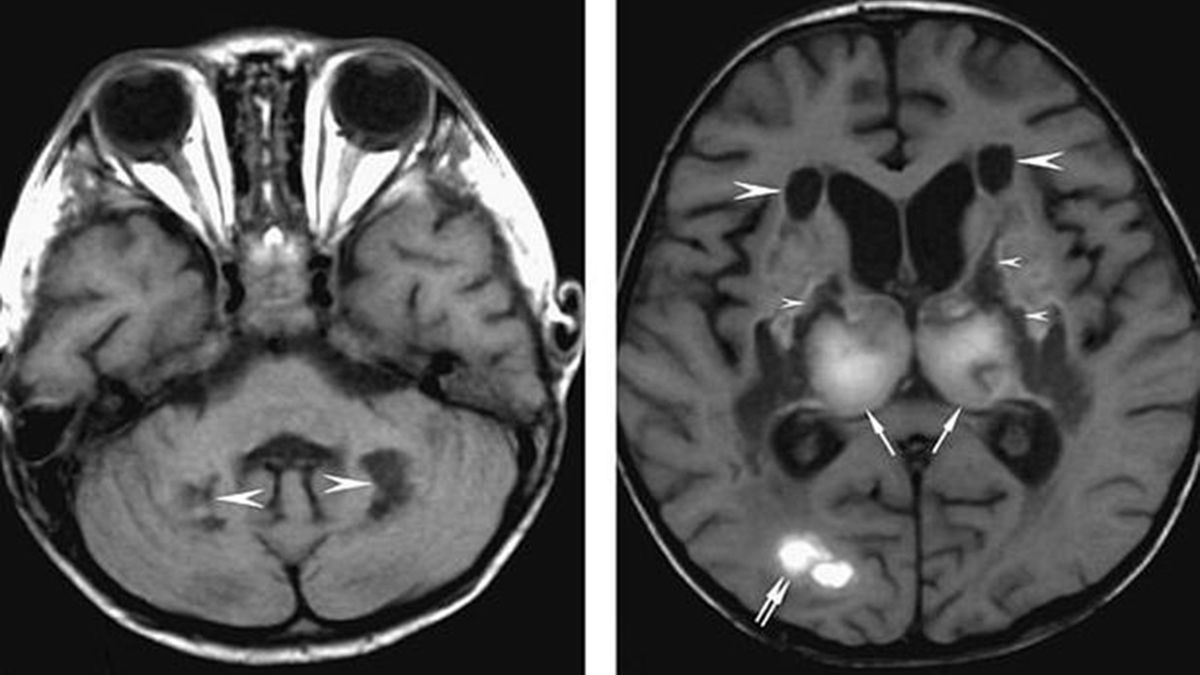

Źródło zdjęć: © Detroit Hospital

Choroba COVID-19 w skrajnych przypadkach może prowadzić do obrzęku mózgu. Te z kolei często powodują tworzenie się krwiaków, krwawienie wewnątrzczaszkowe, a także zanik niektórych komórek mózgowych.

U jednego z pacjentów skutki obrzęku mózgu były bardzo poważne. Mężczyzna stracił umiejętność mówienia - donoszą lekarze ze szpitala na Florydzie.